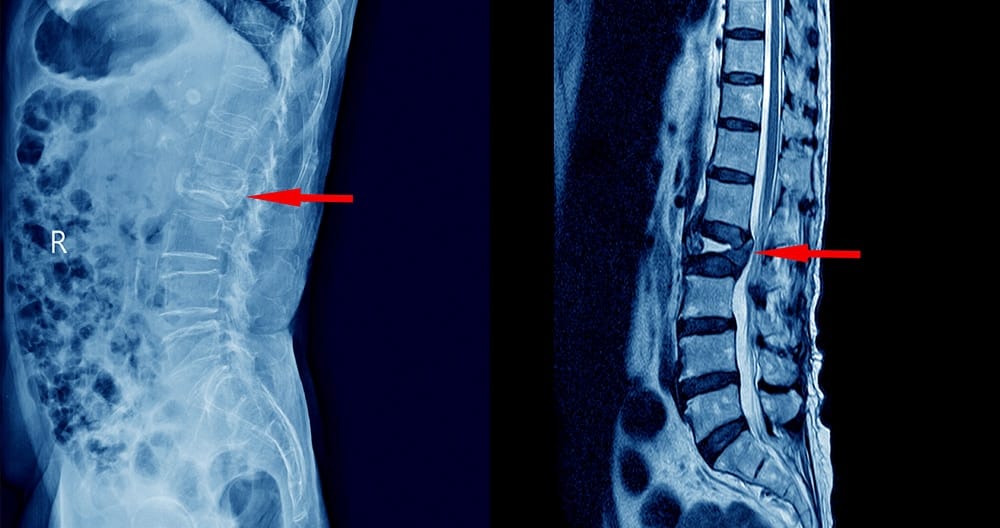

Диагностициране

От изключително значение е поставянето на правилна диагноза. Най-добър и точен метод за доказване на дискова херния е ЯМР.

От рентгенова снимка не може да се видят меките връзки.